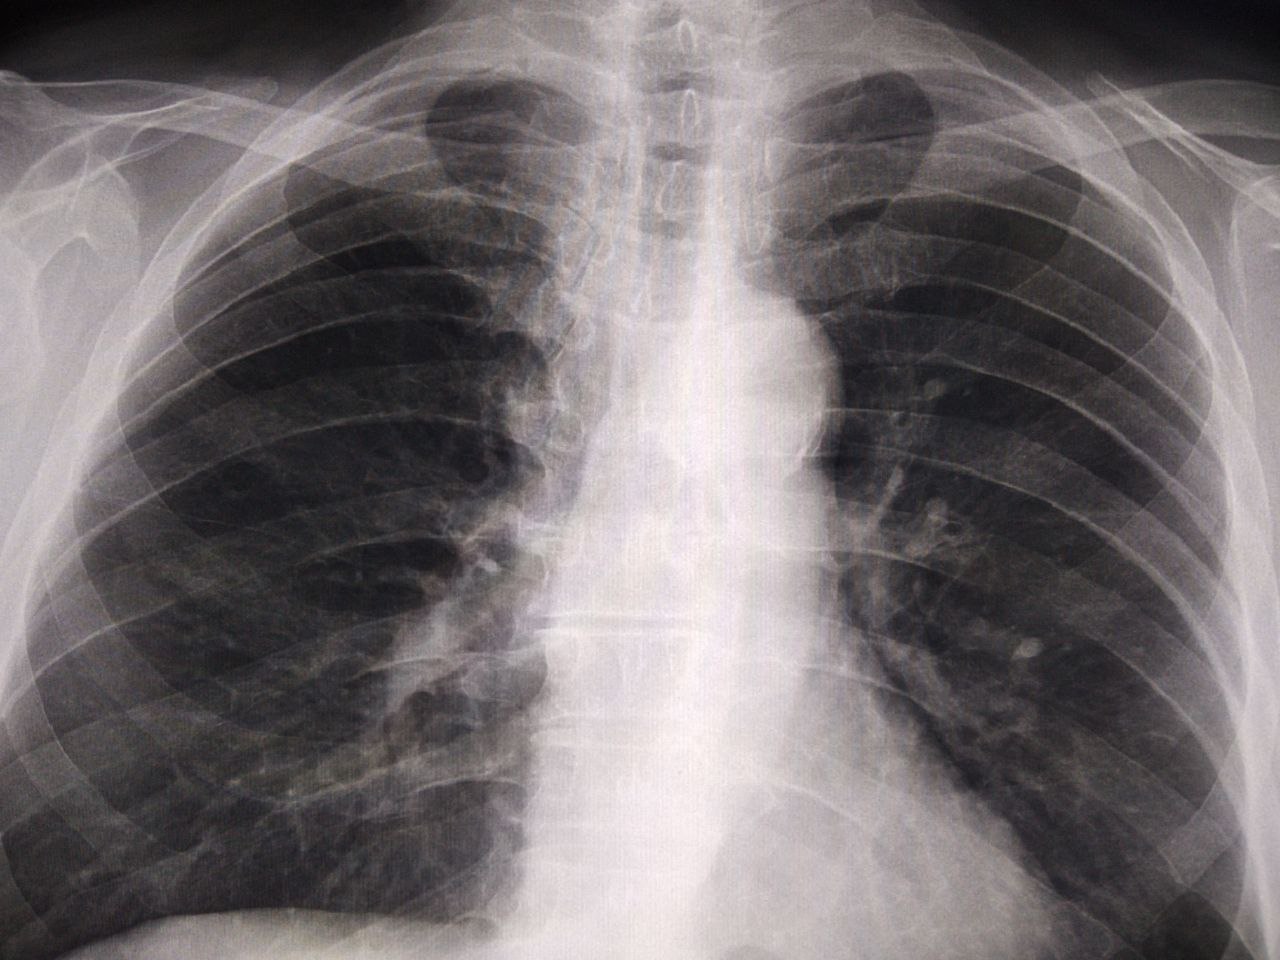

С флг. Затемнения в 3 слева. В прошлом году не было. Проф.цель, т нет. Как можно интерпретировать?